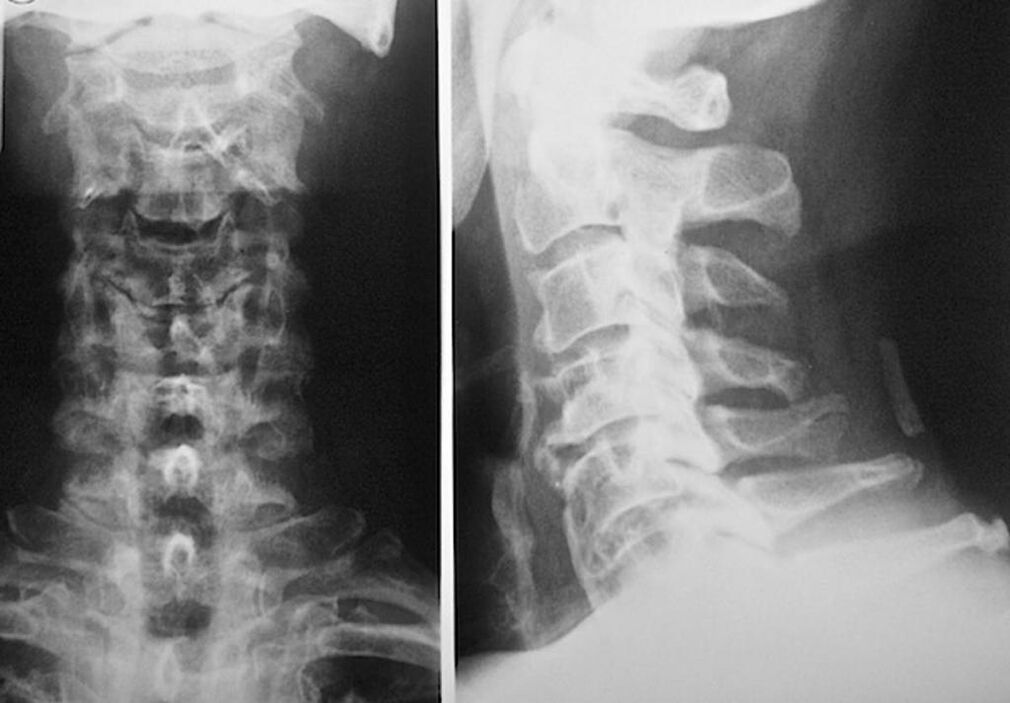

Diagnosis of osteochondrosis: which doctor to contact

To diagnose and prescribe a course of treatment for osteochondrosis of the cervical vertebrae, you need to register for a consultation with a neuropathologist and an orthopedist. A neurologist can prescribe remedies for the manifestations of the disease, which affect the state of the nerve endings. This makes sense if the disease is accompanied by root syndrome. The orthopedist will assess the condition of the spine and diagnose the presence of additional diseases: scoliosis, lordosis, etc.

For the diagnosis and accurate assessment of the state of the intervertebral discs, the following research methods are used:

- Bone scan.

- computed tomography

- Magnetic tomography.

- Sonography of the vessels of the neck.

Each of them is completely safe for health and does not carry any threat of excessive exposure. Diagnosis of osteochondrosis of the cervical vertebrae, the treatment of which will be carried out for the rest of life, can be made after a simple visual examination. Any orthopedist can easily do this. An exception is the first stage of the disease, when no visible pathologies of the cervical region are noted.